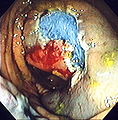

An advantage of colonoscopy over X-ray imaging or other less invasive tests is the ability to perform therapeutic interventions during the test. A polyp is a growth of excess of tissue that can develop into cancer. If a polyp is found, for example, it can be removed by one of several techniques. A snare device can be placed around a polyp for removal. Even if the polyp is flat on the surface it can often be removed. For example, the following shows a polyp removed in stages: